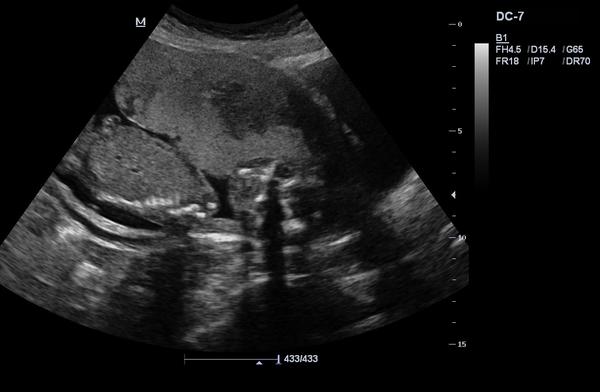

dá se prosím rozpoznat pohlaví?

Pokud ano, tak co myslíte?

bohužel nedá. ☹